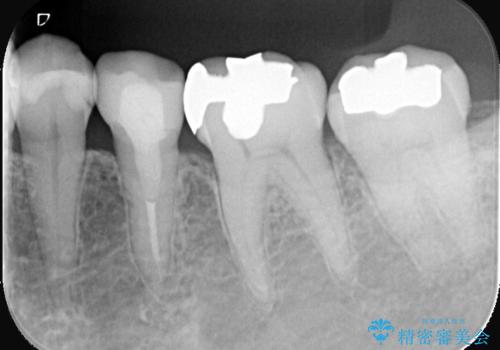

銀歯を白くしたい セラミックインレー

- 銀歯を白くしたいとのことでした。材料の違いを説明し、セラミックインレーでの治療となりました。

接着操作時にラバーダム防湿を行いました。